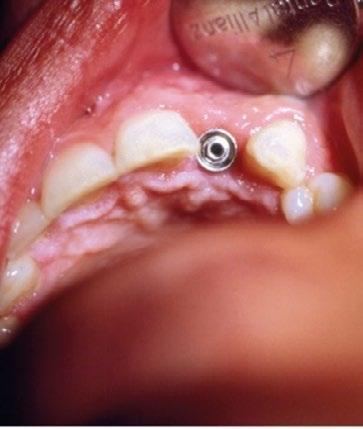

Transcurrido el periodo de cicatrización, se procedió en un segundo tiempo quirúrgico a retirar el tornillo de cierre y a colocar un pilar estándar —habitualmente empleado en prótesis híbridas—, utilizándolo como pilar de cicatrización. (Figura 6)

Ya estabilizados los tejidos, se procedió a la toma de impresiones y a la rehabilitación de ambos incisivos mediante coronas metalcerámicas. Para ello se utilizó el pilar para unitarios diseñado por Torsten Jemt, que, junto con un dispositivo también desarrollado ad hoc, permitía atornillar el pilar ejerciendo un cierto contratorque que hoy en día sabemos innecesario en un implante integrado. (Figura 7)